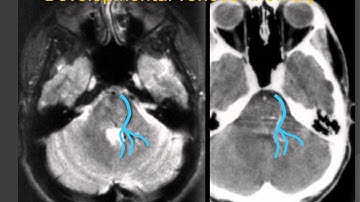

Trigeminal Neuralgia from a Developmental Venous Anomaly